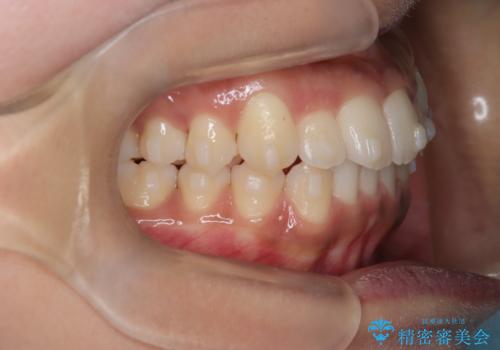

【インビザライン】笑ったときに目立つ八重歯をなおしたい

- 笑ったときに八重歯が見えることを主訴に来院されました。

下の前歯が一本足りない患者様でしたので、シミュレーションを作り、事前に患者様と治療ゴールのイメージをしっかり共有したうえでインビザラインを用いて治療を行っています。

奥歯を後ろのほうに動かすことで、前歯も少し下がることができ、矯正後の口元も満足していただきました。